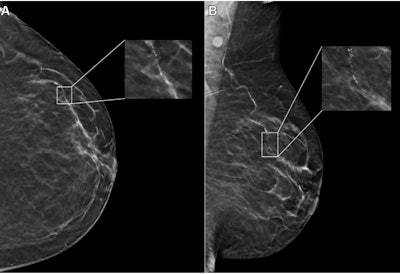

An example mammogram was assigned a false-positive case score of 96 in a 59-year-old Black patient with scattered fibroglandular breast density by an FDA-approved AI algorithm. (A) Left craniocaudal and (B) mediolateral oblique views demonstrate vascular calcifications in the upper outer quadrant at middle depth (box) that were singularly identified by the algorithm as a suspicious finding and assigned an individual lesion score of 90. This resulted in an overall case score assigned to the mammogram of 96.RSNA